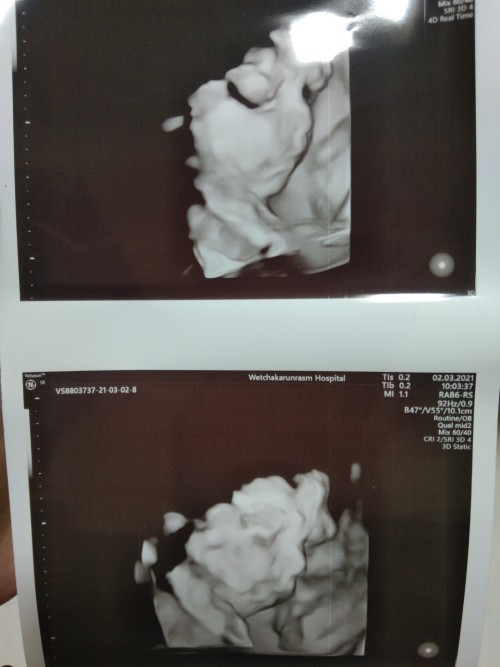

ขอดูแม่ๆทีม มิ.ย 64หน่อยจ้า บ้านนี้ยังไม่รู้เพศเลยค่ะ แม่ๆคิดว่าเพศไหนคะ 26w6d #ขอบคุณสำหรับคำตอบค่ะ #ท้องแรกค่ะ